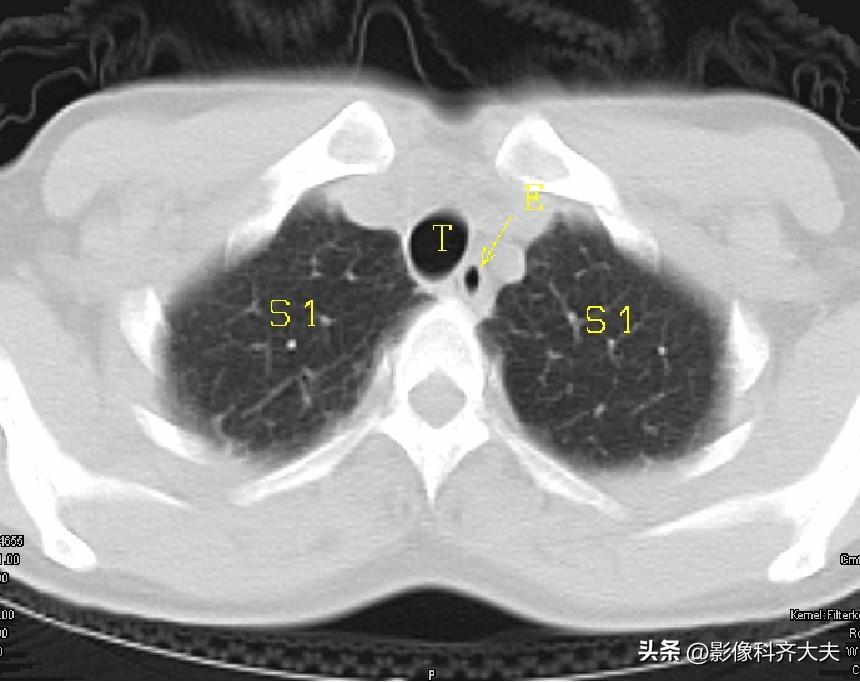

图1-胸锁关节层面

▲T:气管,E:食管,S1:上叶尖段